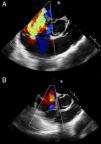

A 40-year-old woman was admitted to the intensive care unit after extensive thoracic burns. During surgical debridement, she experienced rapidly progressive hypoxemia and hypotension requiring high-dose vasopressors, and oxygen saturation remained low despite 100% inspired oxygen concentration. Three-dimensional transesophageal echocardiography was performed, which showed a large thrombus in the right pulmonary artery, extending from the main pulmonary artery bifurcation (Figure 1). It also revealed right ventricular dilatation and severe tricuspid regurgitation (Figure 2A). Given the high bleeding risk associated with recent surgery, a decision was made to perform percutaneous thrombectomy with low-dose intra-arterial fibrinolysis instead of systemic full-dose thrombolysis. Pre-intervention angiography demonstrated a large filling defect in the right pulmonary artery with impaired distal flow (Figure 3A). Abundant thrombotic material was obtained (Figure 3C) and significant improvement in pulmonary circulation was noted (Figure 3B). After the procedure, the patient experienced a dramatic improvement in hemodynamic and respiratory parameters, enabling discontinuation of vasopressors and the use of lower inspired oxygen concentration. Chest radiography demonstrated wedge-shaped pleural based opacities (the “Hampton's hump” sign, Figure 3D). Follow-up echocardiography performed 48 hours later showed resolution of right ventricular dilatation and tricuspid regurgitation (Figure 2B).

Transesophageal echocardiography is useful in the diagnosis of pulmonary embolism in critically ill patients. It may show signs of right ventricular overload and enables direct visualization of thrombi in the right heart or the pulmonary artery. High-risk patients (e.g. those with hemodynamic instability) usually benefit from thrombolytic therapy, but percutaneous techniques are a reasonable alternative when there is significant risk of major bleeding.